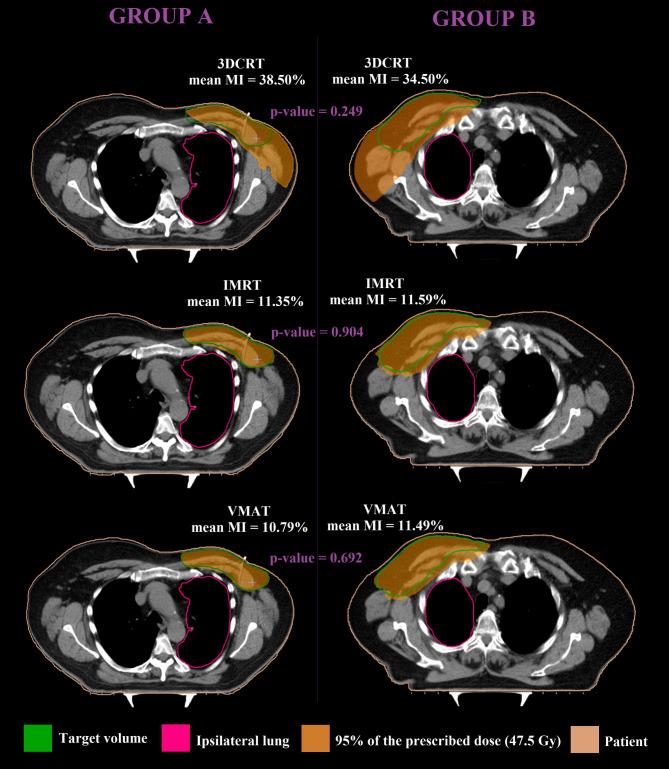

Treatment planning parameters in radiotherapy are key elements that dictate the success of treatment outcome. While some parameters are commonly evaluated irrespective of cancer type, others are site-dependent and strongly patient specific. Given the critical influence of planning parameters on personalized therapy, the aim of this study was to evaluate the correlations between the dosimetric indices (conformity, homogeneity and mismatch indices) related to tumor coverage and the patient-specific parameters which encompass parameters pertaining to organs at risk (widths and lengths of heart and ipsilateral lung included in treatment fields, mean/maximum doses to heart, ipsilateral lung, left anterior descending aorta and contralateral breast) and tumor volume. Forty breast cancer patients were divided into two groups according to tumor location: twenty with left-sided (group A) and twenty with right-sided breast cancer (group B). Conformal (3DCRT), intensity modulated (IMRT) and volumetric arc modulated (VMAT) radiotherapy techniques were used for plan creation. Moderate to strong correlations were found for ipsilateral lung parameters for both groups of patients regardless of the treatment technique. Moderate to strong correlations were found for heart parameters in group A patients, while no correlations were observed in group B. The mismatch index presented moderate to strong correlations with tumor volume for all treatment techniques (r = -0.861 3DCRT, r = -0.556 IMRT, r = -0.533 VMAT) particularly in group A. The evaluated correlations indicate the role of dosimetric indices in personalized treatment planning.

将 40 名乳腺癌患者根据肿瘤位置分为两组:20 名左侧乳腺癌患者(A 组)和 20 名右侧乳腺癌患者(B 组)。采用三维适形放疗(3DCRT)、调强放疗(IMRT)和容积旋转调强放疗(VMAT)技术进行计划制定。

无论治疗技术如何,两组患者的同侧肺参数均显示出中度至强相关性。A 组患者的心脏参数也显示出中度至强相关性,而 B 组患者则无相关性。对于所有治疗技术,不匹配指数与肿瘤体积之间均显示出中度至强相关性(r = -0.861 3DCRT、r = -0.556 IMRT、r = -0.533 VMAT),特别是在 A 组中。